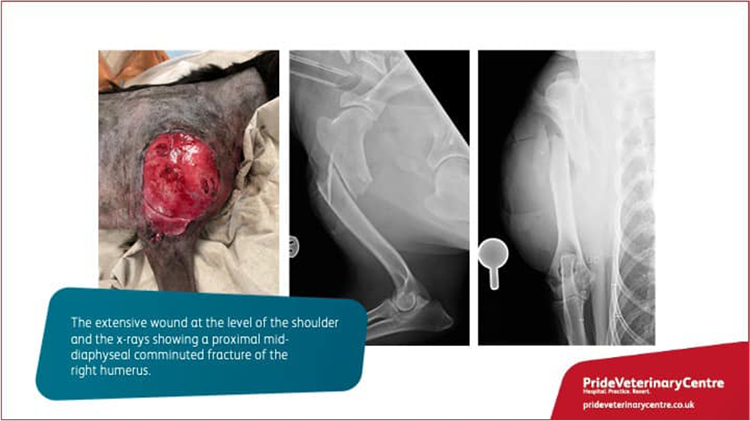

Loki was diagnosed with a comminuted open fracture of the right humerus associated with a large skin wound on the lateral aspect of the shoulder.

Surgery of humeral fracture fixation by a External Skeletal Fixator (ESF) was performed by our Surgery Specialist Rosario Vallefuoco.